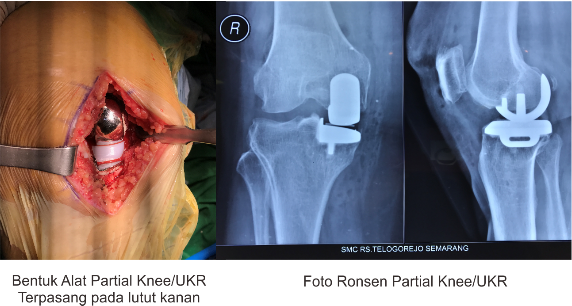

Khusus untuk penggantian sendi lutut sebagian yang dikerjakan di SMC/RS Telogorejo umumnya menggunakan alat desain/produksi negara Inggris dengan teknologi mobile bearing dimana bantalan sendi buatan dapat bergerak mengikuti gerakan permukaan sendi buatan sehingga menambah lingkup gerak sendi dibandingkan versi standar.

Gambar  Sendi Lutut Sebagian/ UKR Unicondylar Knee Replacement Gambar Perbandingan  Luka Operasi Sendi Lutut Sebagian  dan Sendi Lutut Total